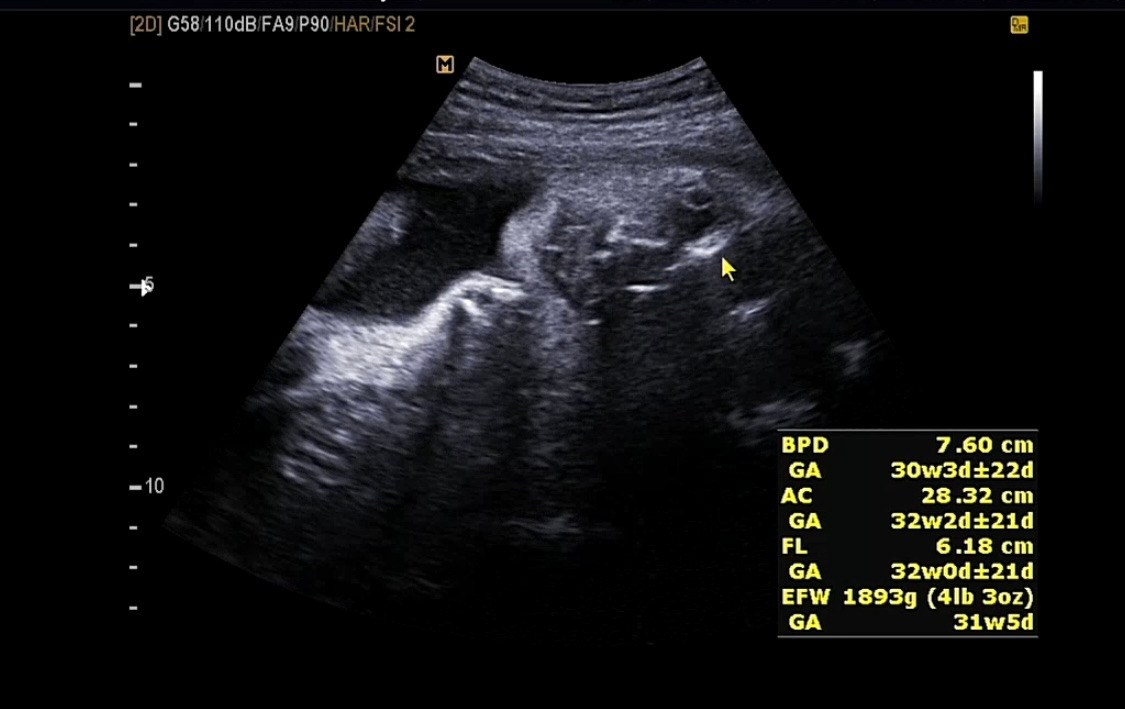

그 사이 궁금해서 남편과 함께 다른 병원을 방문했었다. 너무 오랫동안 다올이를 못 봤었기 때문에 얼마나 컸는지 궁금하기도 했고 어차피 백일해 주사를 맞으러 다른 병원을 갈 예정이었기 때문에 겸사겸사 다올이와 인사하고 왔다.

33주성장기록.png

그사이 열심히 커버린 우리 다올씨

기특하다 기특해